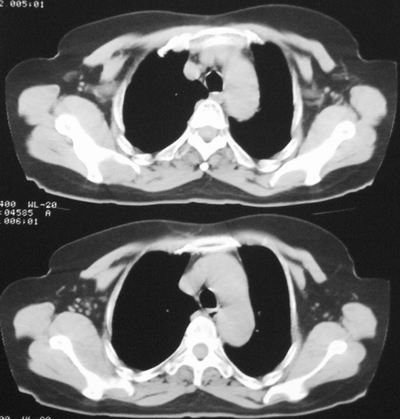

左下肺癌伴左肺门淋巴结转移

支持考虑左下肺原发性肺癌,并左肺门淋巴结肿大

左下周围型肺癌伴左肺门淋巴结及右肺转移可能性大.

左下肺软组织块影,有分叶、毛刺、空泡及胸膜牵拉征,左下肺周围性肺癌。

左肺下叶周围型肺癌,支持!(软组织肿块+分叶+毛刺+空泡+胸膜凹陷征)

左下肺后基底段实性肿块,周围有毛刺,病变周围有肺气肿,与降主动脉间有条带状影相连,病灶4年前查体发现,纵隔内未见肿大淋巴结。考虑.肺隔离症,建议增强扫描与周围型肺癌鉴别。